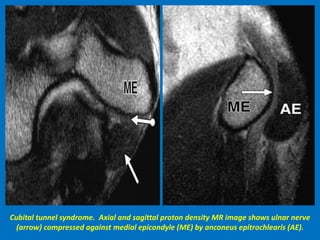

Cubital tunnel syndrome. Axial and sagittal proton density MR image shows ulnar nerve

(arrow) compressed against medial epicondyle (ME) by anconeus epitrochlearis (AE).

Cubital tunnel syndrome.